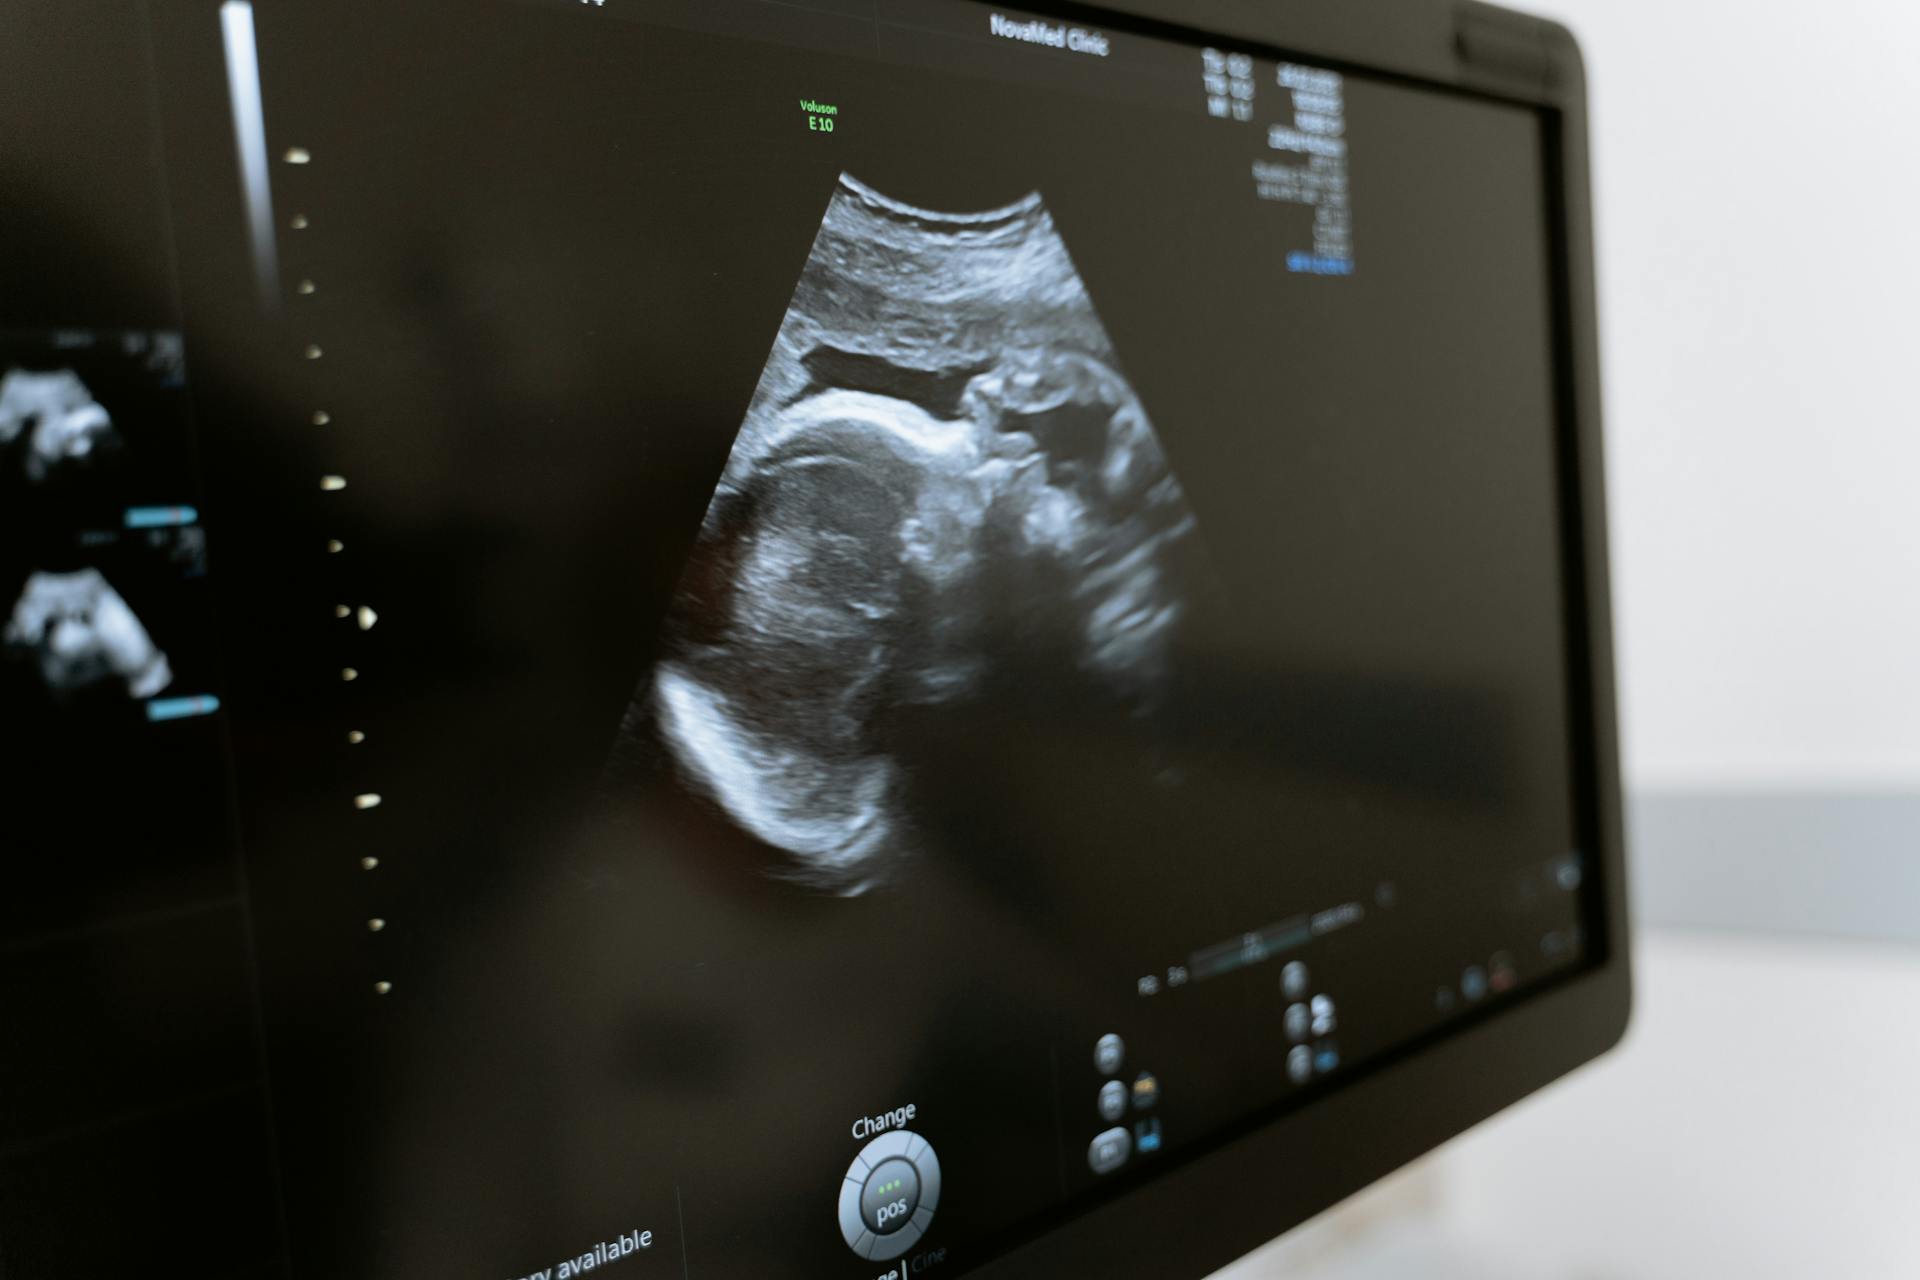

Imagistică ecografică modernă pentru diagnostic rapid și precis

Ecografia este o metodă imagistică non-invazivă, sigură și accesibilă, folosită pentru evaluarea organelor interne, vaselor de sânge și țesuturilor moi. Oferă informații esențiale pentru diagnostic, monitorizare și prevenție, fără radiații și fără disconfort pentru pacient.

Secția utilizează echipamente de ultimă generație, cu rezoluție înaltă și funcții avansate (Doppler, elastografie, mod 3D/4D), ceea ce permite identificarea rapidă și precisă a afecțiunilor. Fiecare investigație este adaptată pacientului, cu timp dedicat evaluării și explicații clare, într-un mediu centrat pe confort și siguranță.

Echipa medicală realizează o gamă completă de ecografii — abdominale, tiroidiene, mamare, părți moi, pelvine, urologice și Doppler vascular — acoperind atât evaluări de rutină, cât și investigații complexe. Serviciile includ și ecografie în regim de urgență, pentru situații acute sau dureri abdominale severe.